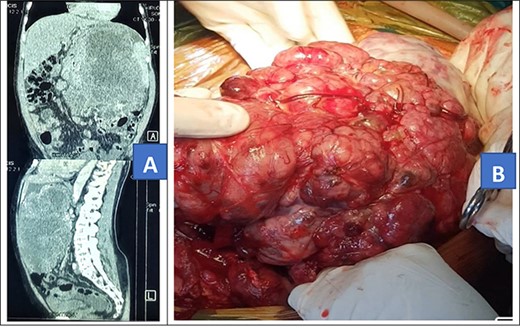

On examination, he was fair, with a temperature of 36.4°C, a pulse rate of 72 beats per minute and had a blood pressure of 128/85 mmHg. The abdomen was grossly distended with a palpable mass in the left upper quadrant. He had no hepatomegaly, He had normal bowel sounds. Other systems’ exam was grossly normal. An abdominal CT was done and it showed a 25.8 × 19.6 × 15.3 cm mass in the left upper abdominal quadrant (Fig. 2A). The patient was scheduled for an exploratory laparotomy.

Preoperative abdominal CT scan (A) and intra-operative picture (B) for Patient 2.

Intra-operatively, a giant 28 × 30 cm retro gastric mucinous tumor was found involving the greater curvature of the stomach, the spleen and part of the left hemi diaphragm (Fig. 2B). The patient was also found to have moderate ascites of 500 ml. The tumor was mobilized and resected. In addition, the greater curvature of the stomach, part of the left hemi diaphragm and spleen were resected. Diaphragm was repaired with ethylon 1–0.